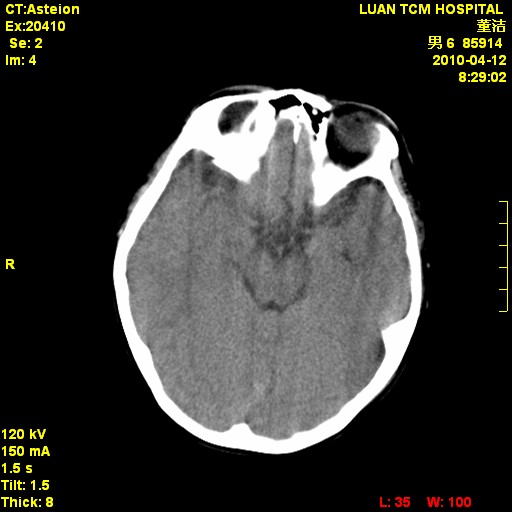

标题: PED3404:有结果,先猜猜这是啥病表现?男,12岁。 [打印本页]

标题: PED3404:有结果,先猜猜这是啥病表现?男,12岁。

无病史无骨窗,无水肿无占位征象,先猜颅骨血管瘤或者嗜酸性肉芽肿

无病史无骨窗,12岁可以可考虑白血病等。

鉴别:骨肉瘤、ewing's瘤、骨淋巴瘤、板障型脑膜瘤、嗜酸性肉芽肿等